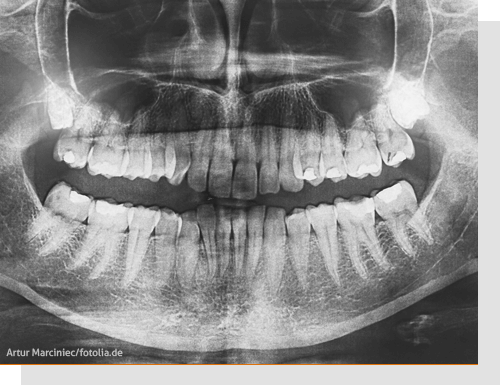

Panoramaaufnahme

Eine Panoramaaufnahme (Orthopantomogramm, kurz OPG) ist eine Übersichtsaufnahme der Zähne und der Kiefer. Auf diesem Röntgenbild lässt sich erkennen:

- ob einer oder mehrere Zähne nicht angelegt sind und im bleibenden Gebiss fehlen werden

- wie die Zähne geformt sind

- wie die Zahnwurzeln im Kiefer liegen ob Weisheitszähne vorhanden sind und ob sie eventuell später entfernt werden sollten

- ob fehlende Zähne möglicherweise vorhanden sind (retinierte Zähne), sie aber z. B. nicht herauswachsen, weil im Kiefer zu wenig Platz ist

- ob noch nicht herausgewachsene Zähne schief im Kiefer liegen (verlagerte Zähne).

Bei Kindern und Jugendlichen sind außerdem schon die sich entwickelnden Zähne im Kiefer sichtbar (die so genannten Zahnkeime). Und es ist zu sehen, wie weit die Zahnwurzeln der bleibenden Zähne bereits gewachsen sind.